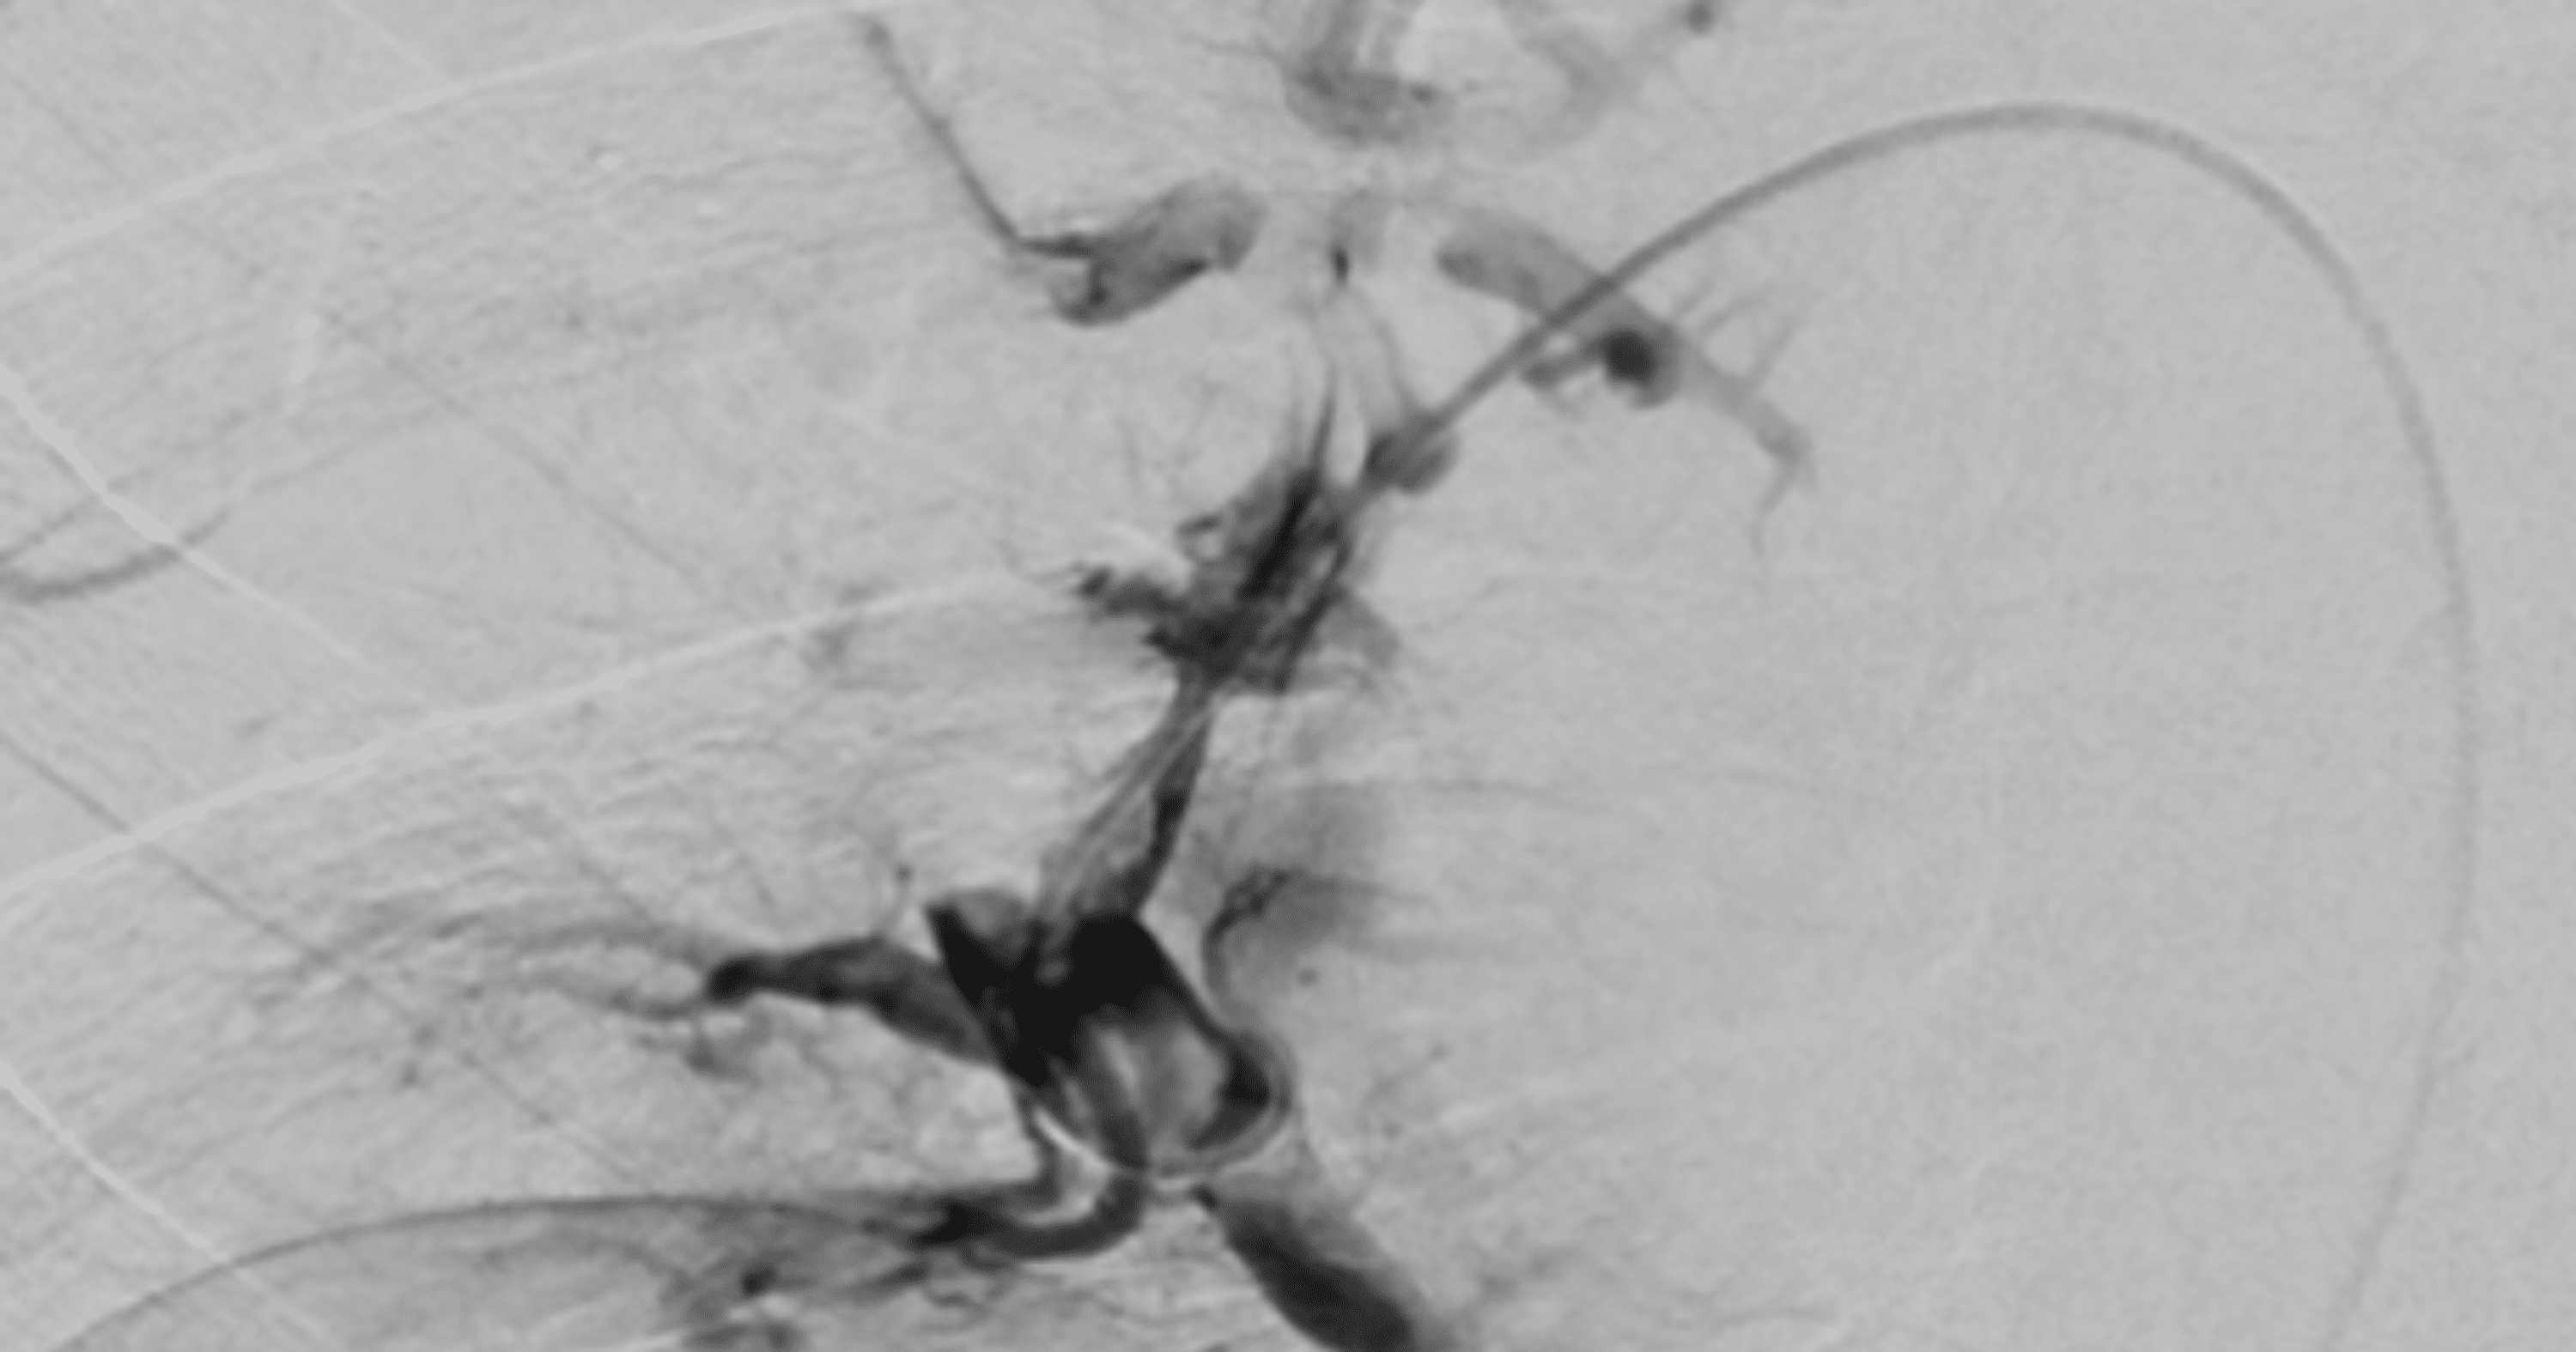

Imaging of fluoroscopyguided thrombolysis. The 5French pigtail Catheter Guided Thrombolysis A recently published prospective registry of 101 patients with acute pe (perfect [pulmonary embolism response to fragmentation,. Catheter Guided Thrombolysis.